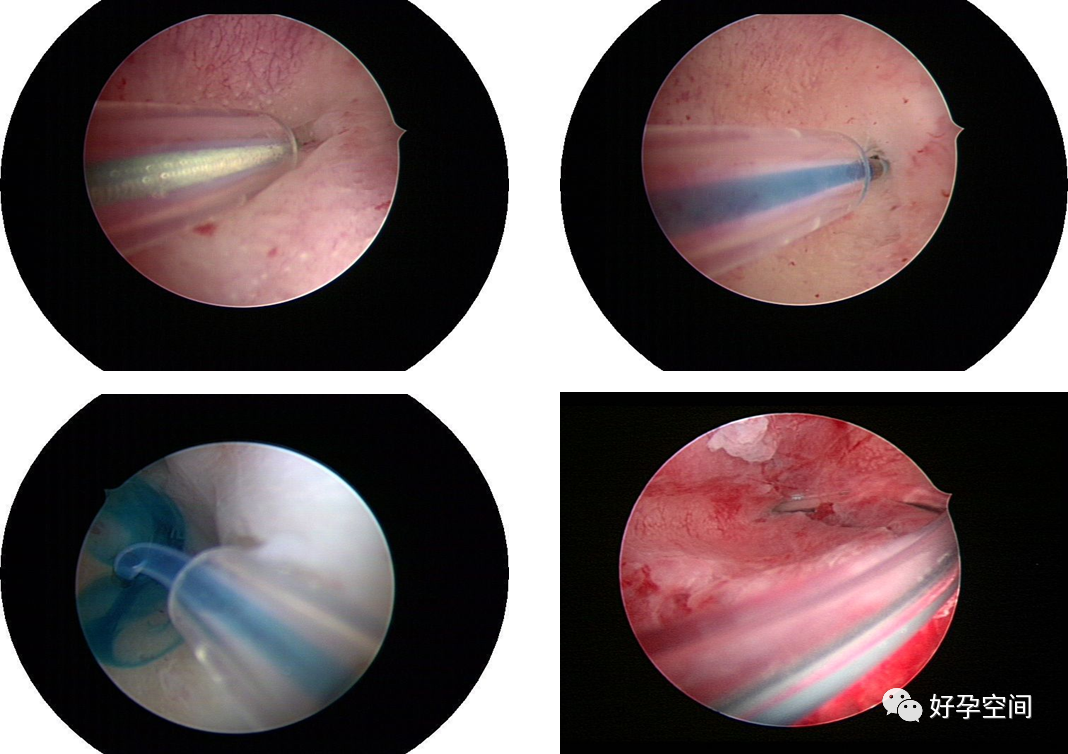

6、宫腔镜输卵管开口电凝封堵绝育、输卵管开口置入弹簧圈封堵绝育、胚胎移植前阻断输卵管积水返流入宫腔。

试管助孕前双侧输卵管积水,腹腔镜及开腹手术失败,宫腔镜电针电凝封堵输卵管开口

既往试管助孕前输卵管开口植入弹簧圈,再次移植前宫腔镜检查,弹簧圈包埋组织内,不见痕迹